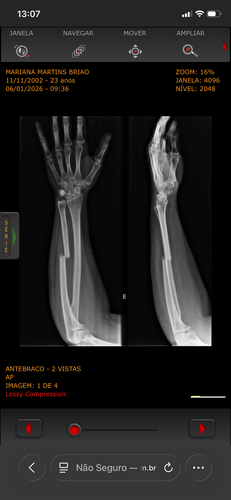

Eu acabei quebrando o calcanhar e o braço, vou precisar passar por duas cirurgias para colocar placas e ficarei uns meses sem poder me locomover e trabalhar infelizmente.